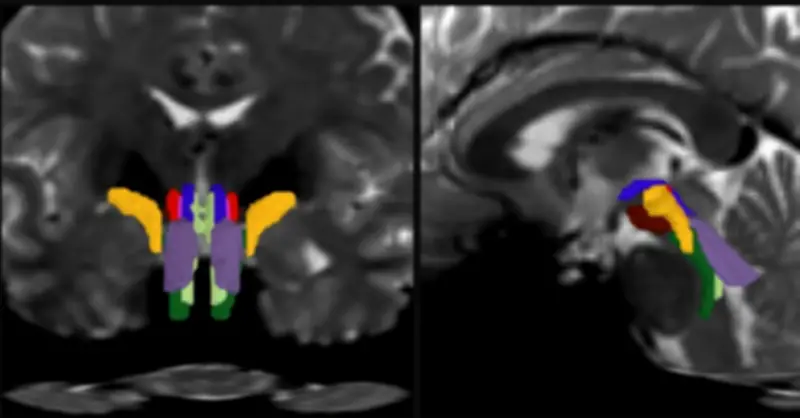

- Sau đó, một mạng nơ-ron tích chập tích hợp bản đồ này với nhiều lớp dữ liệu hình ảnh khác để phân biệt tám bó sợi riêng biệt.

Để huấn luyện mô hình, nhóm nghiên cứu sử dụng 30 bộ dữ liệu diffusion MRI từ Dự án Human Connectome, được chú thích thủ công nhằm “dạy” AI nhận diện chính xác các bó sợi. Kết quả được kiểm chứng bằng cách so sánh với các mẫu giải phẫu não người sau tử vong, vốn được phân định rõ dưới kính hiển vi hoặc qua hình ảnh siêu phân giải.

Sau giai đoạn huấn luyện, BSBT có thể tự động xác định tám bó sợi trong các bộ dữ liệu mới. Khi thử nghiệm trên 40 tình nguyện viên được chụp hai lần cách nhau hai tháng, công cụ này liên tục xác định chính xác cùng một hệ bó sợi ở mỗi cá nhân. Nhóm nghiên cứu cũng kiểm tra chéo trên nhiều bộ dữ liệu độc lập và đánh giá riêng từng thành phần của mạng nơ-ron để bảo đảm độ tin cậy.